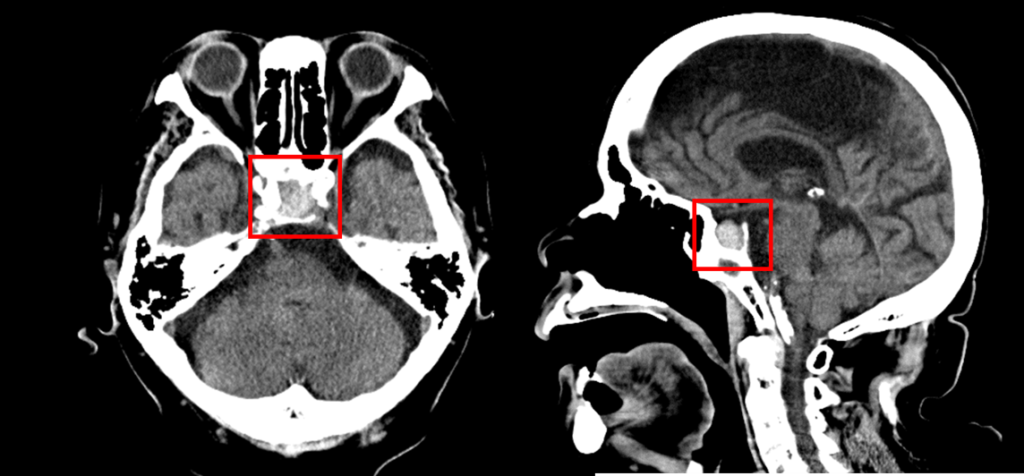

その時の頭部CT画像です。

放射線科医の読影レポート

「下垂体には頭尾径14mmの高吸収域があり、血腫が示唆されます。」

臨床情報を加味すると、まずは下垂体卒中が疑われます。

脳外科/神経内科的にご加療の上、状態が落ち着かれたら背景の腫瘍性病変検索のため造影MRIをご検討ください。

とのことでした。

搬送直後の頭部単純CTでは、救急科の医師によって脳出血や急性期脳梗塞はないと判断されましたが後日、放射線科医の読影レポートによって下垂体内の高吸収域(出血)が指摘され、MRI検査が追加検査されました。